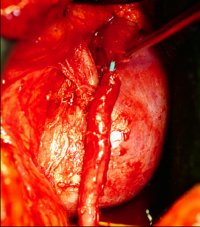

Die Nierenfreilegung ergab ein aberrierendes Gefäß. Die Abbildung zeigt schematisch das strangulierende Gefäß und das gestaute Nierenbecken (Abbildung 8).